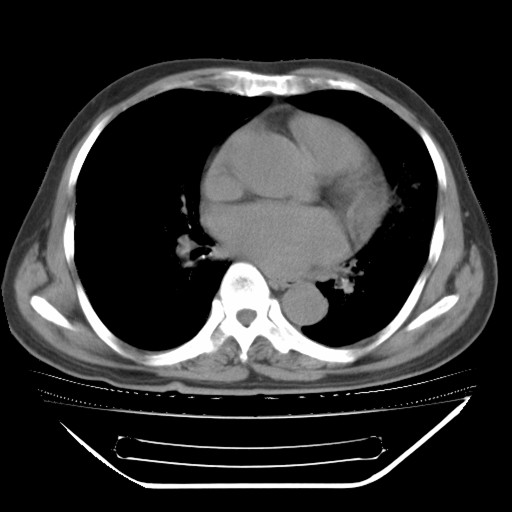

以下是引用hhcckk在2009-5-29 10:34:00的发言:[br]左下肺片絮状边缘模糊影,考虑感染,建议治疗后复查[br]